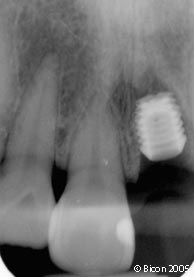

46. | 就位的一体化基台冠戴入后的X光片。 |